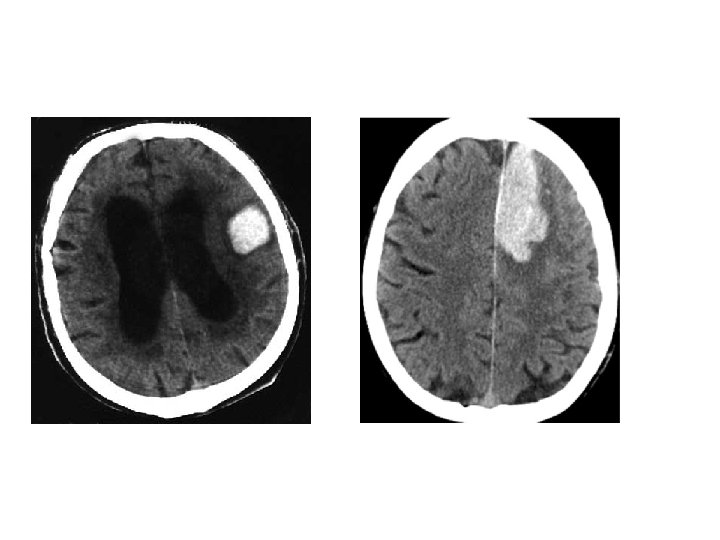

Lobar Hemorrhage • 神經學表現依血塊大小及出血位置不同而 有所不同 • Contralateral hemiparesis or sensory loss, aphasia, neglect, or confusion • Headache is common, disturbance of consciousness is milder